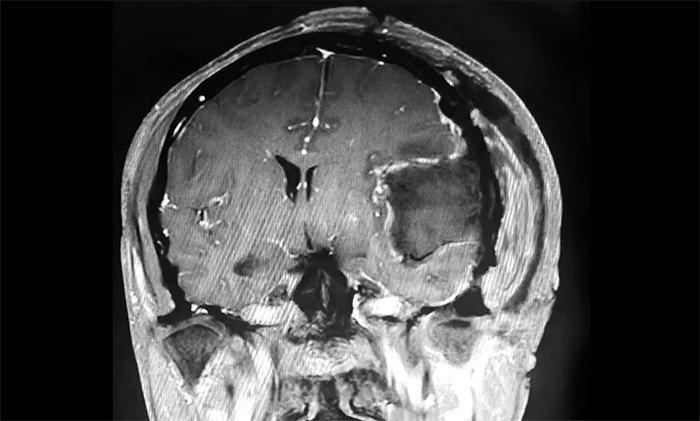

▲ 腫瘤順利切除

手術取左側額顳頂部入路,在顯微鏡下,沈建康主任與於耀宇主任通力協作,仔細分離腫物周邊密集的神經血管,逐步分塊切除腫物及附着的硬膜。切除腫瘤後,術區瘤腔未見活動性出血。歷時5小時,手術順利完成,留取病理標本送檢。

術後,患者生命體徵平穩,安返監護病房。經對留取的腫物樣本進行病理分析,確定為纖維型腦膜瘤(WHO 1級),為良性腫瘤。